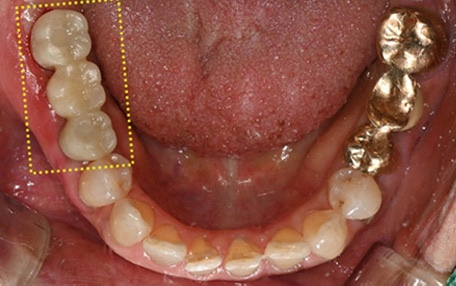

생각보다 많은 분들이 해당되는 치료

상악동 거상술은

아주 특수한 경우에만 진행되는 치료는 아닙니다.

위쪽 어금니 임플란트를 계획하시는 분들 중

검사 과정에서 상악동 거상술이 필요하다는

설명을 듣게 되는 경우가 꽤 많습니다.

특히

치아를 뽑은 지 오래된 경우

위쪽 어금니 쪽 잇몸이 많이 내려앉은 경우

틀니를 장기간 사용했던 경우에는

자연스럽게 고려되는 치료입니다.